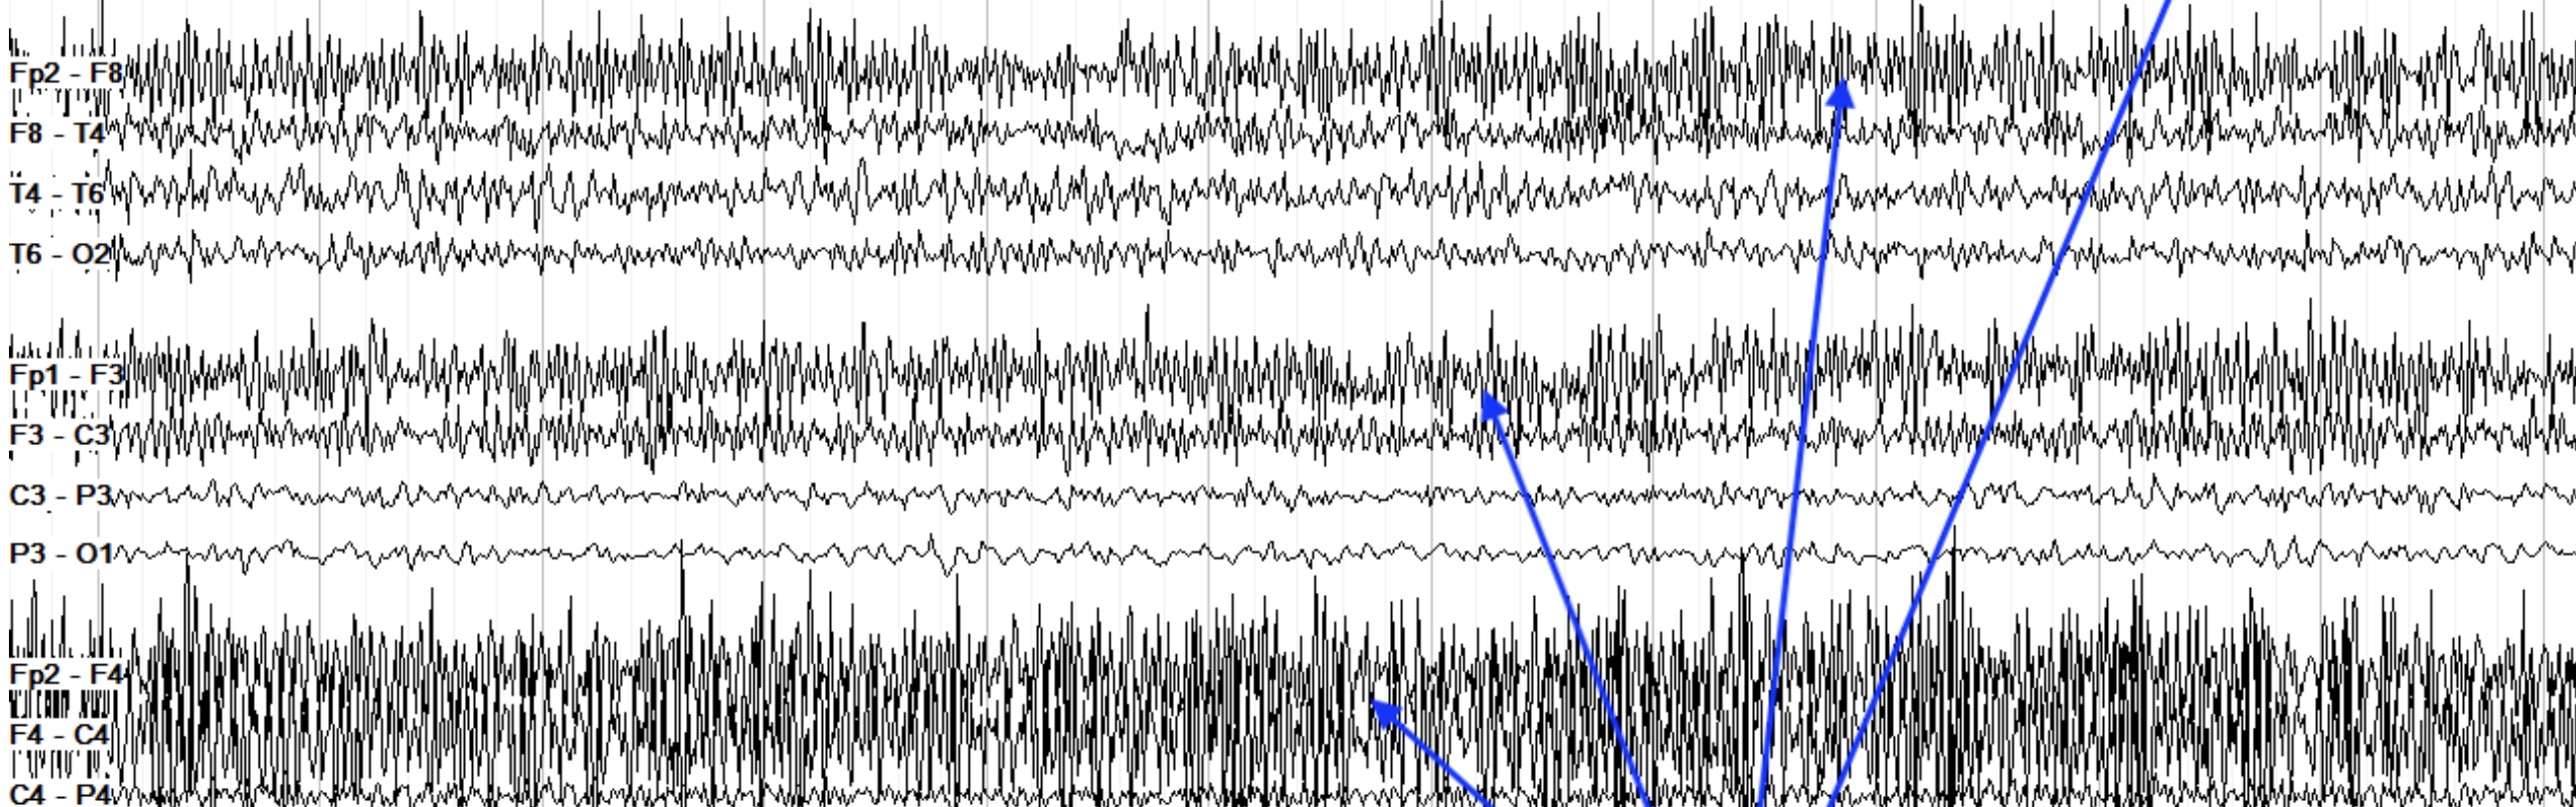

theta spam everywhere synchronized. 3hz→2hz→1.5Hz→0

Generalized Seizure